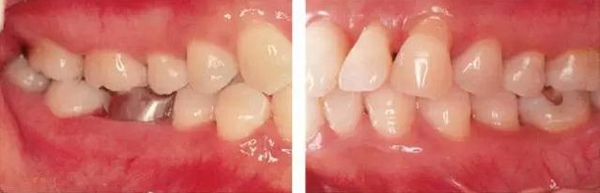

●參考病例① 35歲女性

35歲女性。妊娠4個(gè)月。過(guò)去雖然接受過(guò)刷牙指導(dǎo),但菌斑控制狀態(tài)依然不理想?;颊哂邪l(fā)現(xiàn)自己刷牙時(shí)牙齦出血。